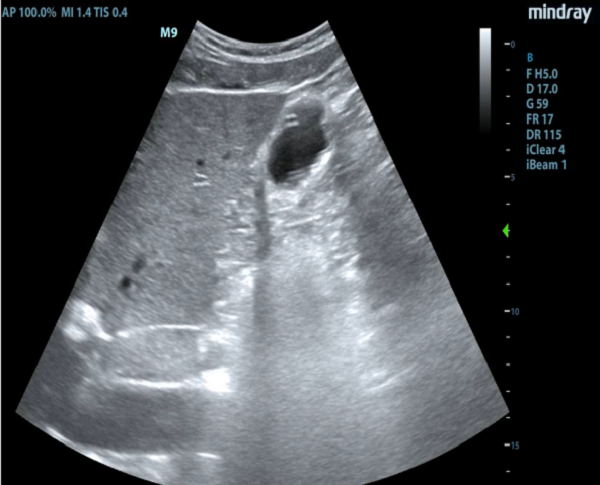

經(jīng)過一系列準(zhǔn)備,根據(jù)超聲顯影,鼻腸管從賁門到通過幽門,動態(tài)調(diào)整徐徐送入空腸,超聲顯示鼻腸管尖端最終到達十二指腸空腸段(圖3、4),整個過程緊張有序,在劉學(xué)松副主任醫(yī)師、普布央金護長及何軍副主任護師的共同努力下,成功為患者置入鼻腸管。

(圖3、4)